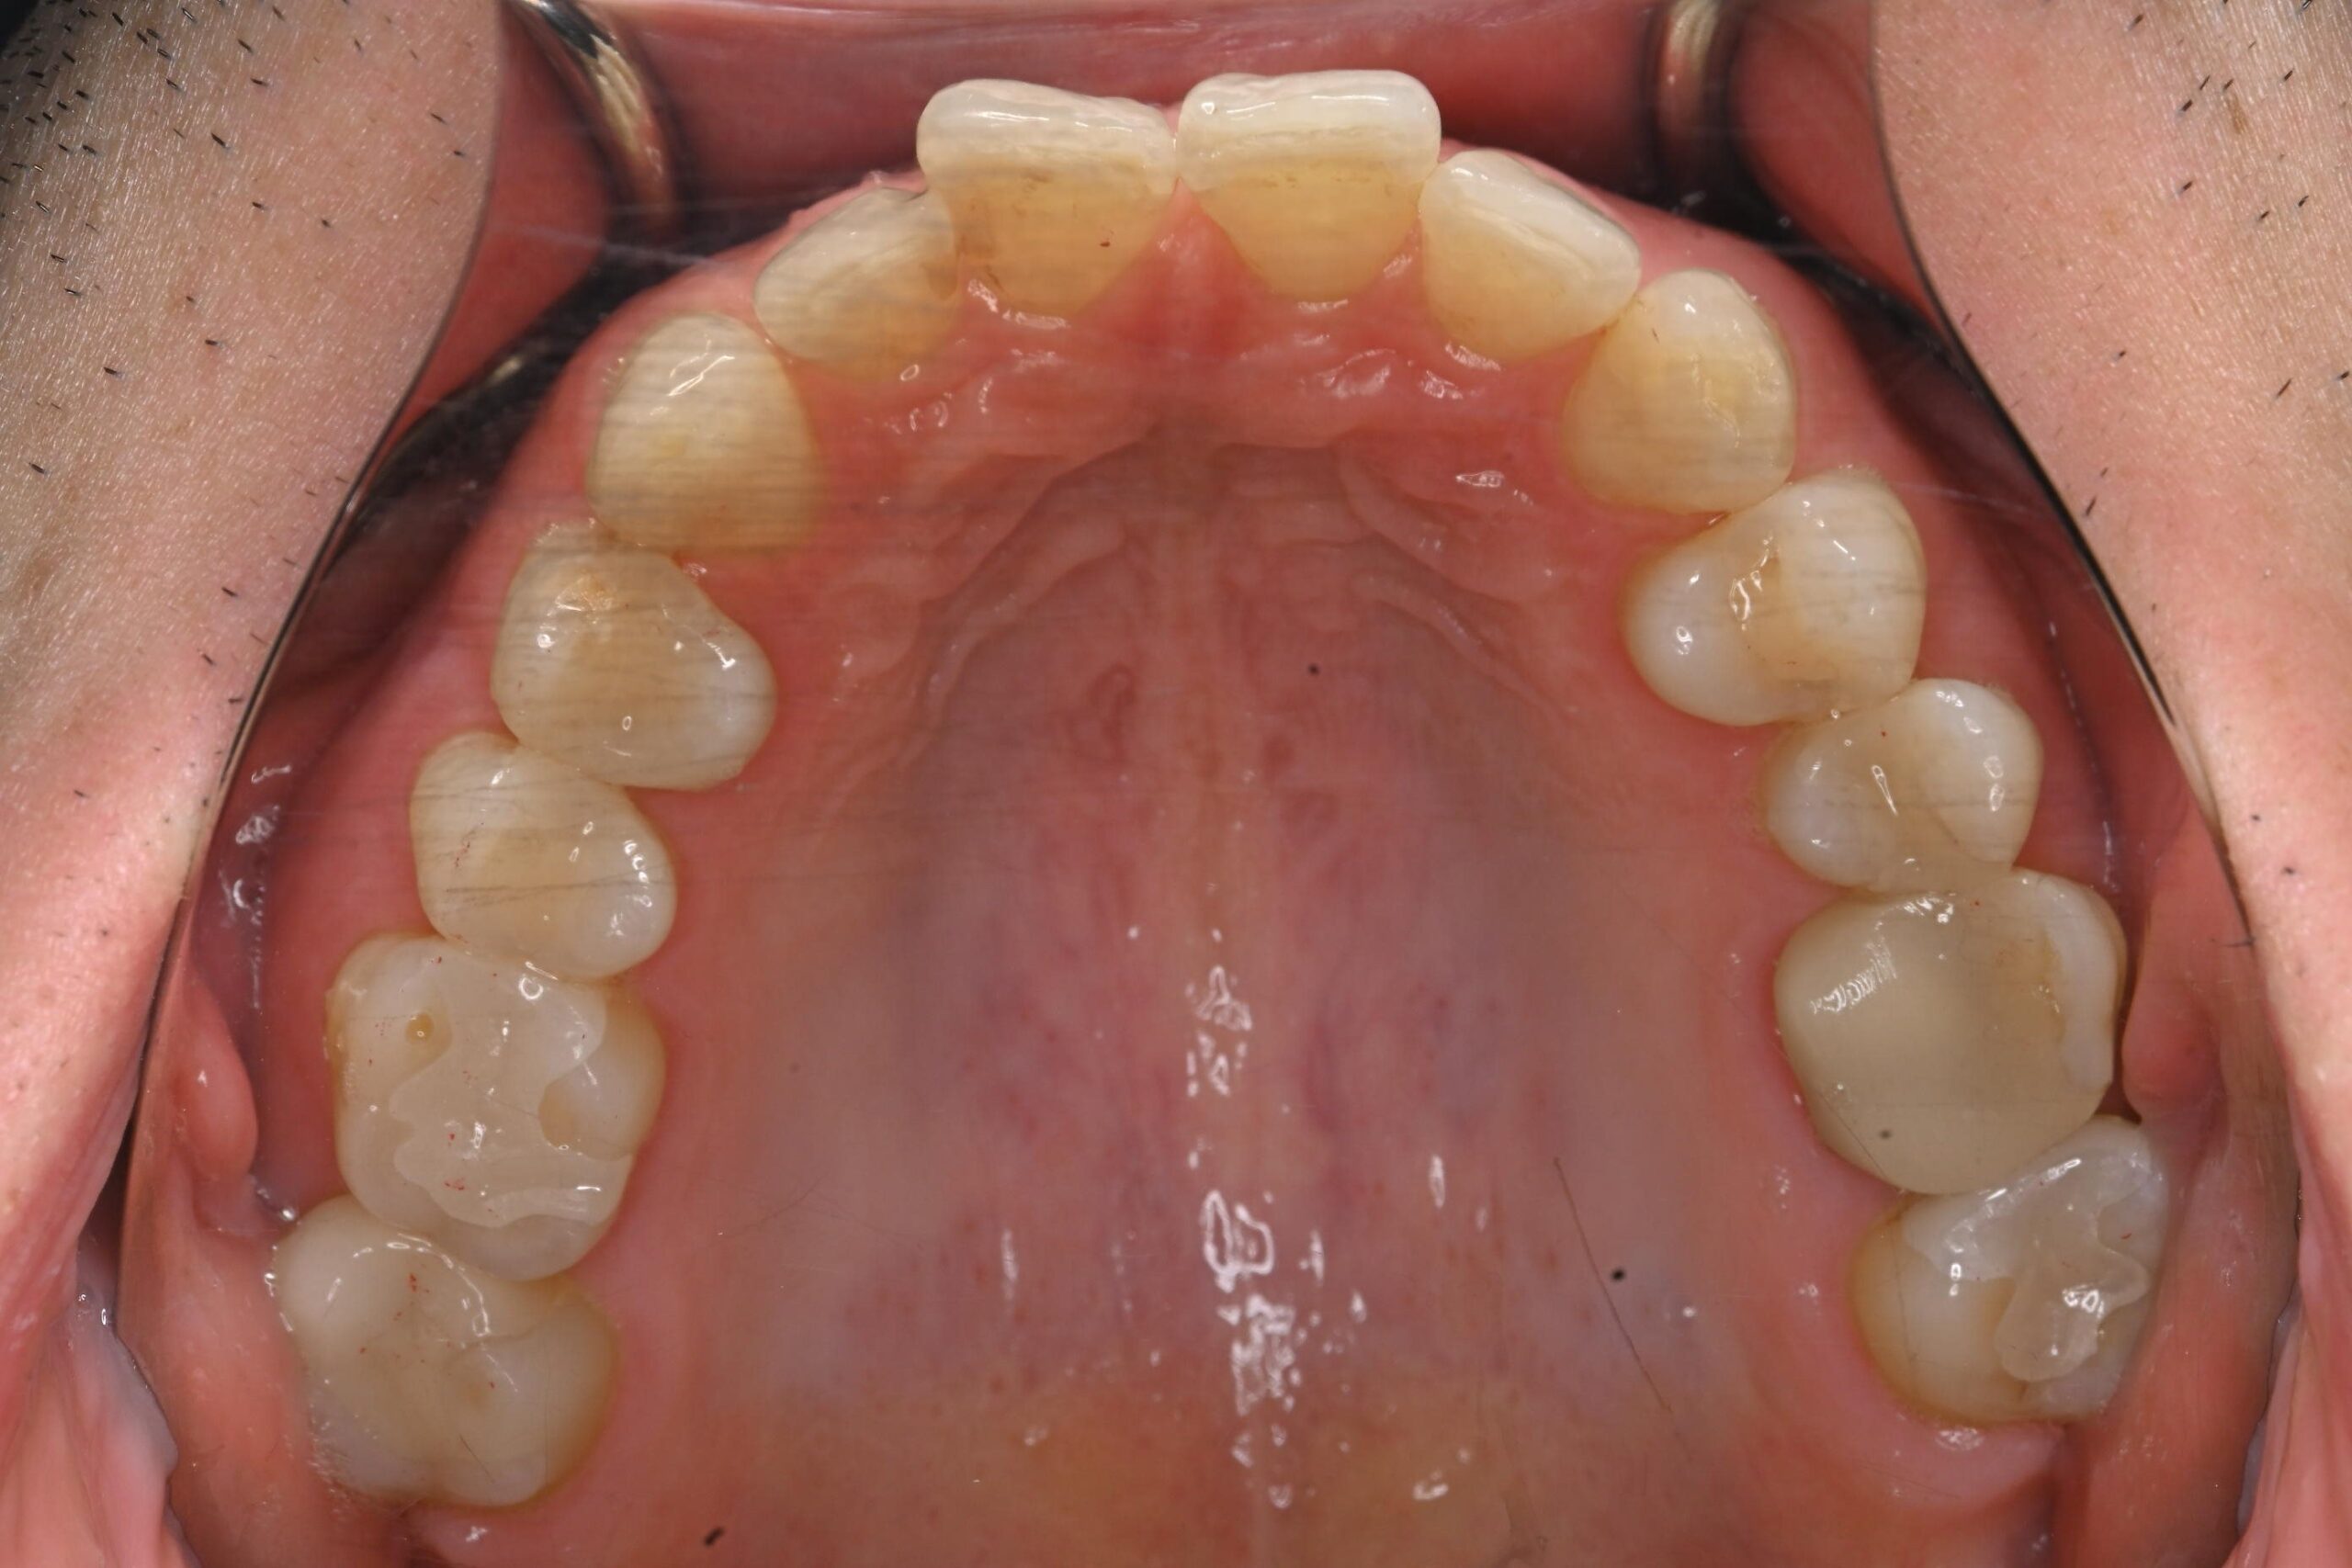

初診時の口腔内の状態:

口腔内には多数の銀歯(銀合金)が確認されました。患者様は過去に多くの虫歯治療を受けており、そのほとんどが保険適用内の銀合金で修復されていました。

患者様はパッチテストによりニッケルなどに対するアレルギーを持っていることが確認されており、口腔内の銀合金もアレルギーの原因となっている可能性が高いと診断しました。また、レントゲン画像を確認すると、被せ物や詰め物の内部、あるいは隙間から、虫歯(カリエス)や根の細菌感染が疑われる状態も確認されました。